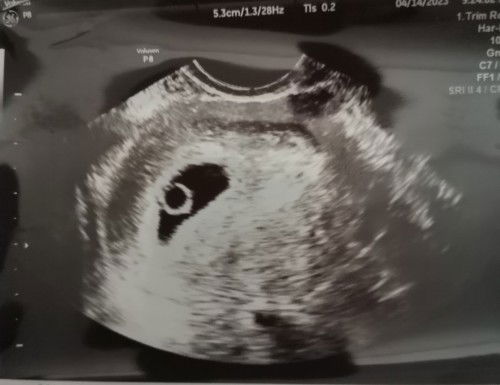

No fetal pole seen

Td pergi emergency sbb bleeding..Dokter scan atas tak nampak sangat then pg tvs scan..Dokter cakap yolk sac seen tp no fetal pole seen😌setakat ni takda cramping.. sy risau sgt sbb ni kandungan kedua lepas gugur tahun lepas..kena jumpa dokter lagi 2 minggu akan datang.. Semoga ada keajaiban🌈